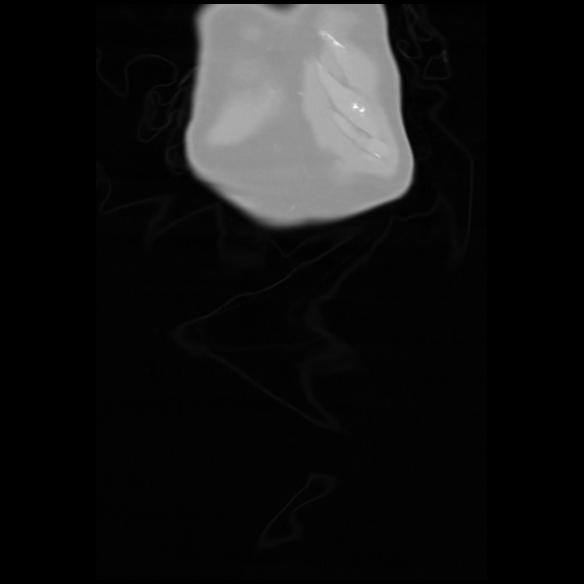

6 CUERPO,CE,Coronal,3.000,CUERPO,Coronal,